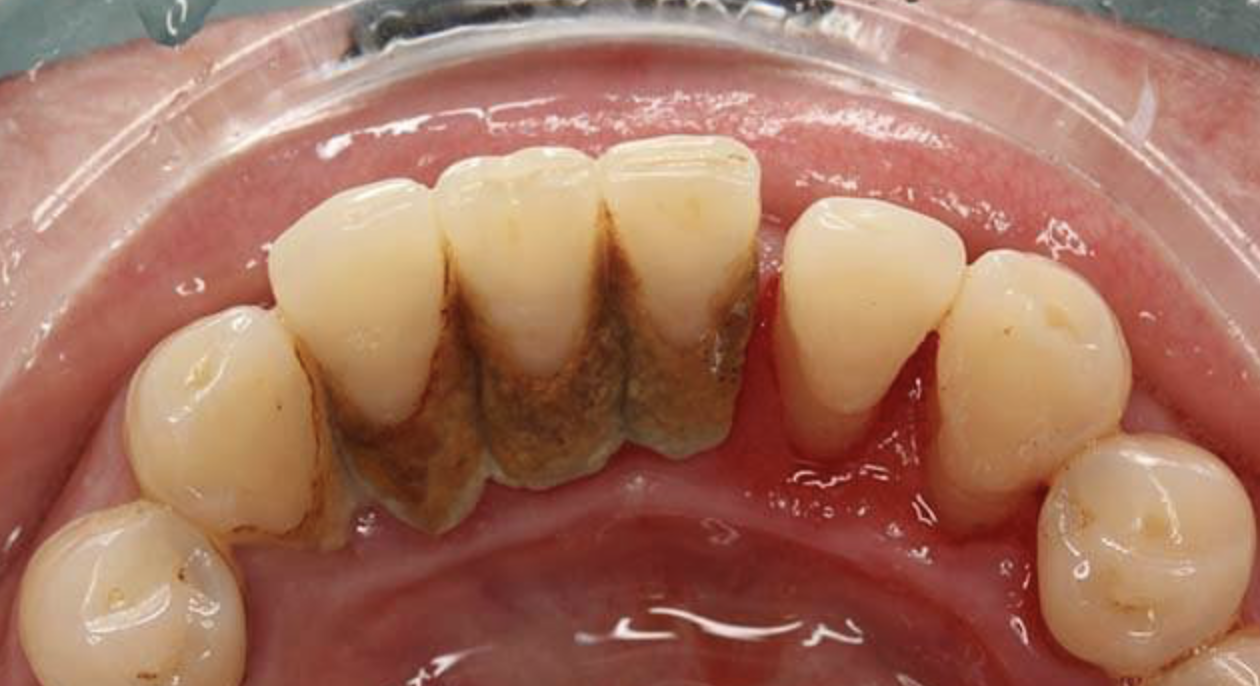

由于口腔科治疗会导致气溶胶悬浮于空气中,在呼吸时会进入呼吸道,导致新冠肺炎感染,所以面对特殊时期,广大民众掌握灵活的牙病自救方法尤为重要。在长假里,牙龈出血与红肿、疼痛,可谓是常见病了,反复牙龈出血是不是得了大病?别急,我们看看麦芽口腔是怎么说的。

麦芽口腔指出,生活中常见的牙龈出血都是牙性的,没有全身性的不适,表现为刷牙、进食、吸吮时牙龈出现渗血。导致牙龈出血的原因除了硬物撞击导致的牙龈受伤,更多是口腔卫生引起的。

尤其针对牙周炎患者来说,存在牙周袋,牙菌斑与牙结石多附着于龈下,尤其容易导致牙龈炎症。